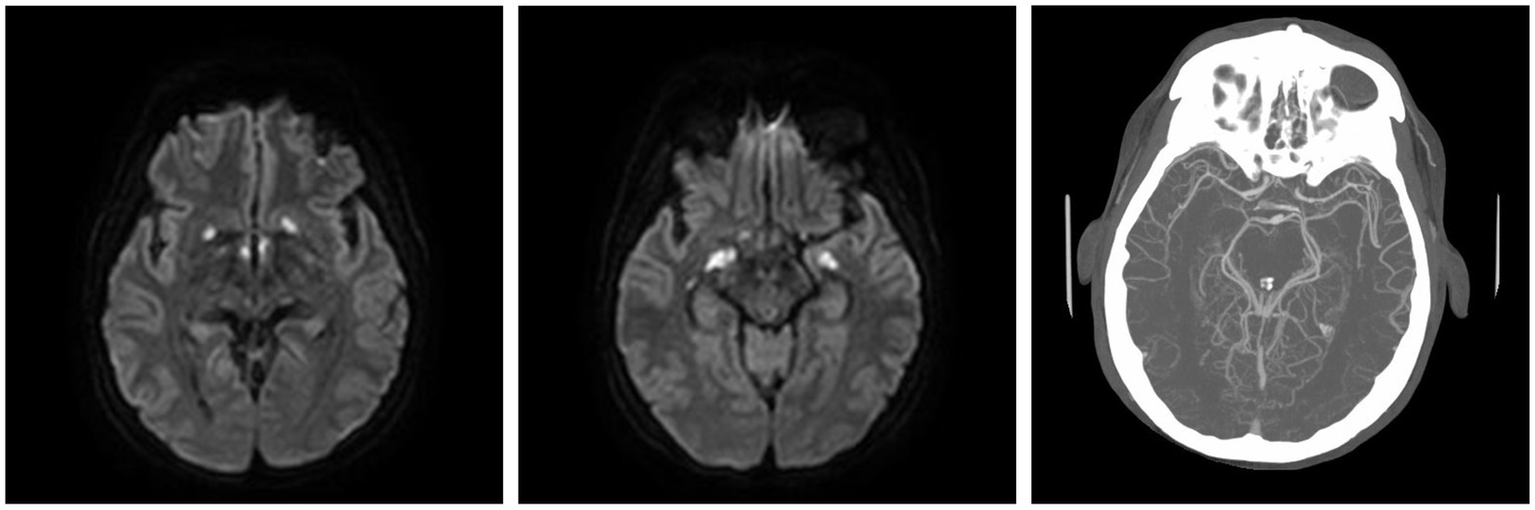

Figure 1

MRI skull base T1 + C at 6-week follow-up with reported improvement of symptoms. (A) Interval increase in the cavernous sinus mass size with extension into the pituitary fossa. (B) Subtle enhancement along V2 on the left, suggesting infiltrative process(inlet). (C) Narrowing of the left ICA.

Moreover, 13 weeks after the initial presentation, he returned to the ED with altered mental status and was admitted for evaluation. On examination, he demonstrated word-finding difficulties, impaired attention, and neck stiffness. No other focal signs were noted. MRI re-imaging demonstrated new leptomeningeal enhancement and acute strokes of the bilateral basal ganglia, hypothalamus, and medial temporal lobes, with vascular imaging demonstrating multifocal stenoses with bilateral ICA involvement (Figure 2). The CSF studies revealed significant neutrophilic pleocytosis with an elevated white blood cell count (WBC) of 3,089 uL (72% polymorphonuclear neutrophils (PMNs)), hypoglycorrhachia (35 mg/dL), and elevated protein (124 mg/dL; Table 1). Infectious workup, including bacterial, fungal, and acid-fast cultures; BioFire Meningitis/Encephalitis PCR panel; Nocardia cultures; cryptococcal antigen; and Toxoplasma PCR, was negative. Broad-spectrum antimicrobials, including vancomycin, ceftriaxone, ampicillin, acyclovir, and amphotericin, were initiated for empiric meningitis coverage, covering typical and atypical bacterial, viral, and fungal meningitides in the setting of a seemingly indolent course. Ampicillin and acyclovir were quickly discontinued due to negative testing. The patient was tapered off outpatient steroids during hospitalization. Despite serial CSF studies showing an improving cell count (Table 1), symptoms continued to worsen, leading to a comatose state, which resulted in the patient being intubated and transferred to the intensive care unit on hospital day 3. Serial imaging showed new and expanding regions of diffusion restriction involving the basilar artery territory, as well as proximal posterior cerebral artery stenosis presumably secondary to vasospasm (Figure 3). Magnetic resonance angiography of the head showed enhancement around the basilar artery, raising concern for infectious vasculitis.

Figure 2

At the ED admission with altered mental status, MRI brain demonstrating basal ganglia and medial temporal infarcts. CTA head demonstrating multifocal stenoses involving bilateral ICA.

Figure 3

MRI brain T1 + C when the patient lost corneal and pupillary reflexes. Subsequently transferred to the ICU. (A) Patchy enhancement within basal ganglia. (B) Worsened leptomeningeal enhancement around the suprasellar cistern. (C) Non-enhancing cystic focus suggesting thrombus or abscess.